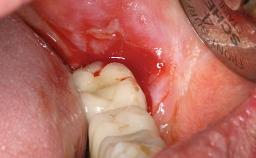

A 24-year-old female patient was treated with an implant- supported crown for single-tooth replacement at site 11. A Straumann Bone Level RC implant (Institut Straumann AG, Basel, Switzerland) was placed with simultaneous bone augmentation, and the periimplant emergence profile was conditioned with a fixed implant-supported provisional crown. After finalization of the mucosal architecture, the clinical situation was transferred by means of a custom impression post for fabrication of an implant-supported screw-retained onepiece crown consisting of a CARES® zirconia abutment (Straumann) with a direct ceramic veneer.